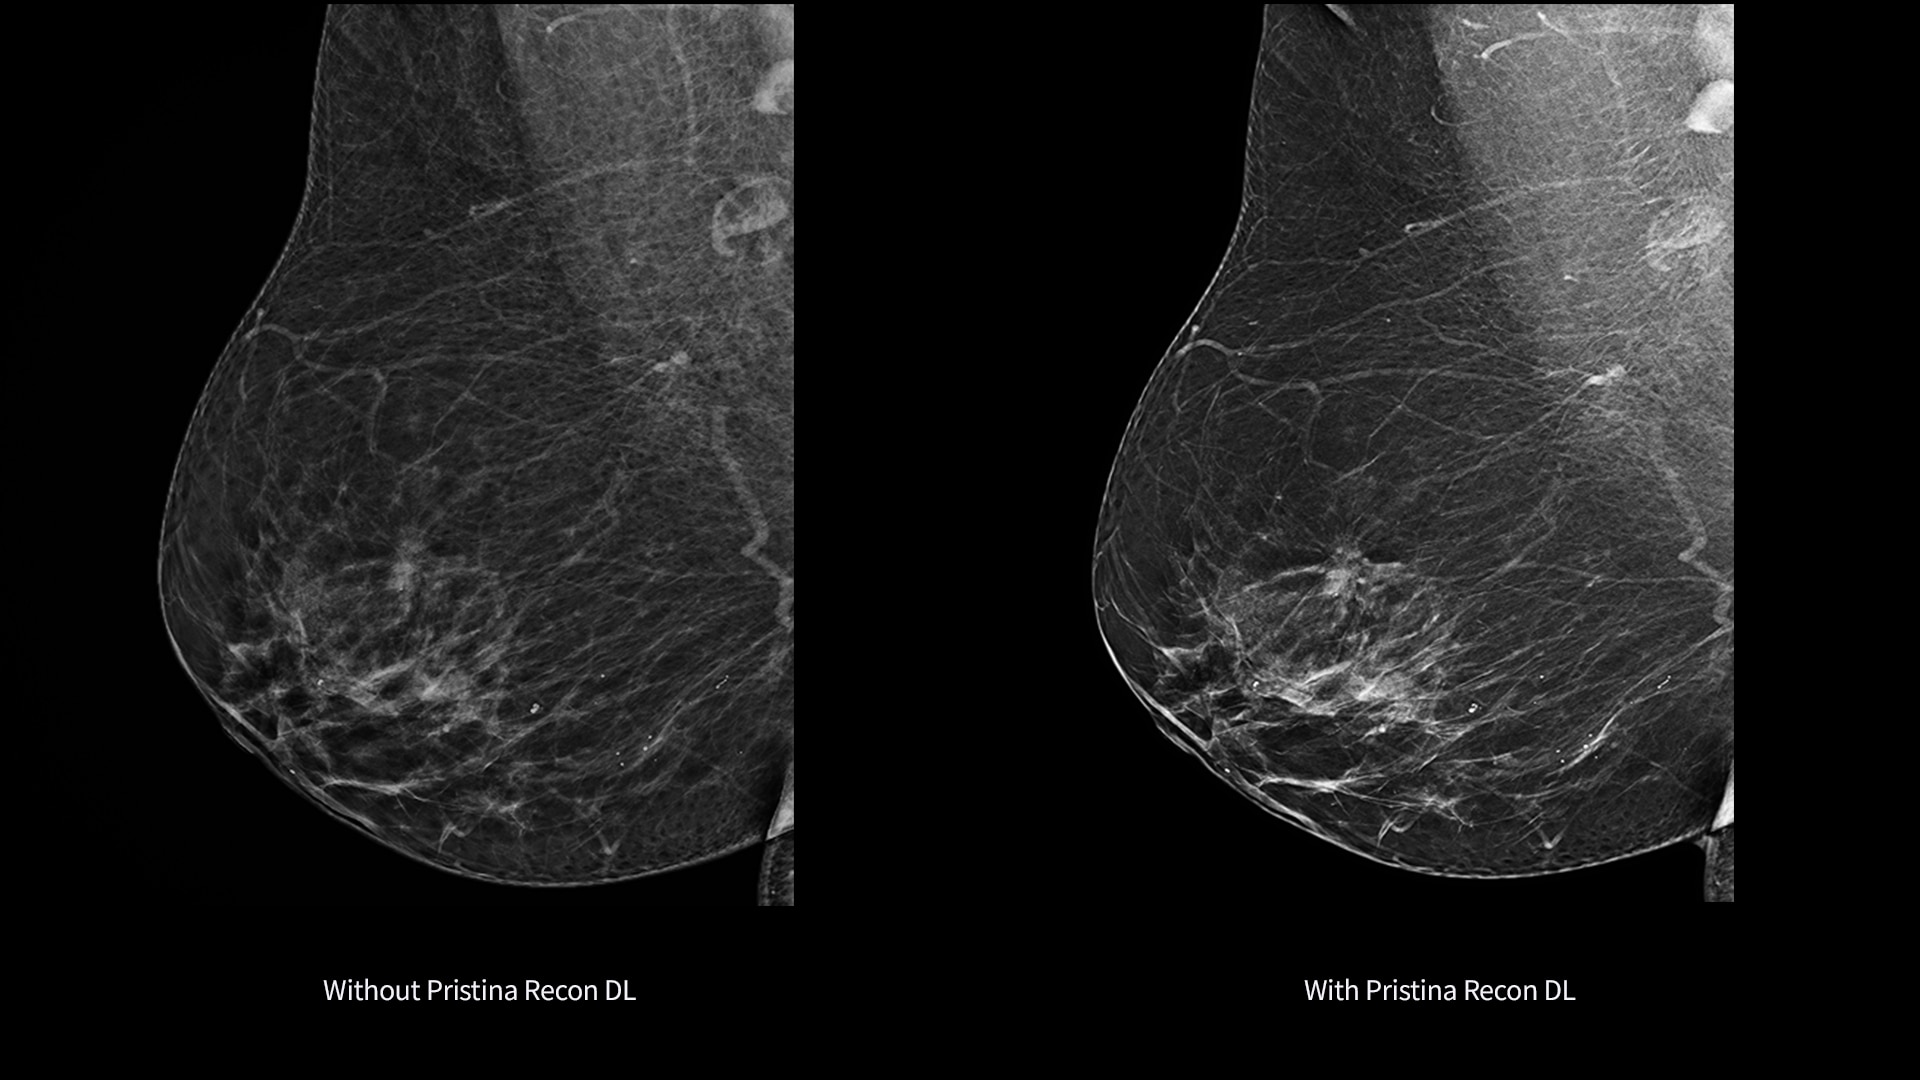

Pristina Recon DL*

The power to detect. The confidence to decide. Introducing groundbreaking technology in mammography image reconstruction, with precision you can see.

Pristina Recon DL gives you the power to detect and confidence to decide.

It pushes the limits of 3D mammography, delivering images with greater purity.

Its dual deep learning technology reveals fine details minimizing artifacts and perceived noise1,2, without increasing dose.

Pristina Recon DL reconstructs with scientific precision, transforming breast images into pristine, clear volumes. It uses two deep learning models to improve image quality without changing the acquisition.

The improvement is easy to see, with radiologists surveyed consistently preferring its sharpness1,2 and lesion conspicuity1,2.